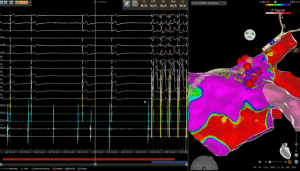

La procedura viene eseguita in un laboratorio di elettrofisiologia, esperto nella esecuzione di procedure complesse, sotto sedazione. Utilizzando vari cateteri e un sistema di ricostruzione tridimensionale delle camere cardiache, il medico accede al cuore attraverso i vasi sanguigni. Una volta evidenziate le terminazioni vagali nei vari punti degli atri, un catetere emette energia (spesso radiofrequenza) per ablare (distruggere) selettivamente i nervi vagali intorno al cuore che causano la bradicardia. L’ effetto sulle terminazioni vagali si manifesta inizialmente con un rallentamento del battito cardiaco, fino alla asistolia (come nel caso della figura 2) e successivamente procedendo sui vari gangli del cuore si assiste ad un progressivo aumento della frequenza cardiaca. Questo permette di ridurre l’influenza nervosa che rallenta il battito cardiaco, stabilizzando il ritmo del cuore.

Figura 2